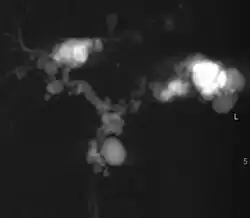

Turbo spin echo T2-weighted axial MRI of Caroli disease, showing cystic dilatations of bile ducts (shown as white).[1] | |

Modern imaging techniques allow the diagnosis to be made more easily and without invasive imaging of the biliary tree.[9] Commonly, the disease is limited to the left lobe of the liver. Images taken by CT scan, X-ray, or MRI show enlarged intrahepatic (in the liver) bile ducts due to ectasia. Using an ultrasound, tubular dilation of the bile ducts can be seen. On a CT scan, Caroli disease can be observed by noting the many fluid-filled, tubular structures extending to the liver.[4] A high-contrast CT must be used to distinguish the difference between stones and widened ducts. Bowel gas and digestive habits make it difficult to obtain a clear sonogram, so a CT scan is a good substitution. When the intrahepatic bile duct wall has protrusions, it is clearly seen as central dots or a linear streak.[10] Caroli disease is commonly diagnosed after this “central dot sign” is detected on a CT scan or ultrasound.[10] However, cholangiography is the best, and final, approach to show the enlarged bile ducts as a result of Caroli disease.